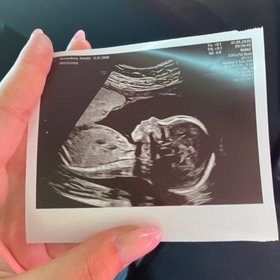

Dnes oznámila Natálie Kočendová tragickou zprávu na svých sociálních sítích. V šestém měsíci těhotenství přišla o svého syna, kterého čekala s Lukášem Vlačuhou neboli Laky Royalem. Modelka také sdílela svou první a poslední fotografii s miminkem, které se mělo narodit za 3 měsíce. K partnerce se později přidal i její přítel, který zveřejnil snímek z ultrazvuku.